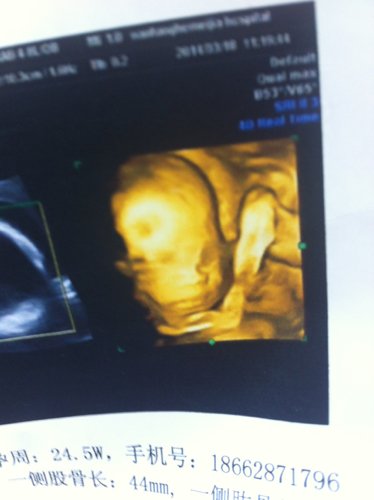

帮忙看下这两张四维彩超图有问题吗?是不是鼻子和眼睛不对劲啊?急急 点击展开 匿名用户 2014-04-07 12:16 为您推荐: 其他回答 病情分析: 您好,四维彩超上面就是这样的 指导意见: 如果自己有什么不明白的地方建议您最好还是咨询下自己的医生吧。 匿名用户 2014-04-07 16:26 相关问题 帮忙看下这两张是怀孕24周做的四维彩超图,感觉鼻子和眼睛有问题、你们认为有什么问题吗? 七个月的宝宝鼻子上眼睛上怎么像张斑是的 胎儿颜面可显示是不是鼻子和眼睛就没有问题